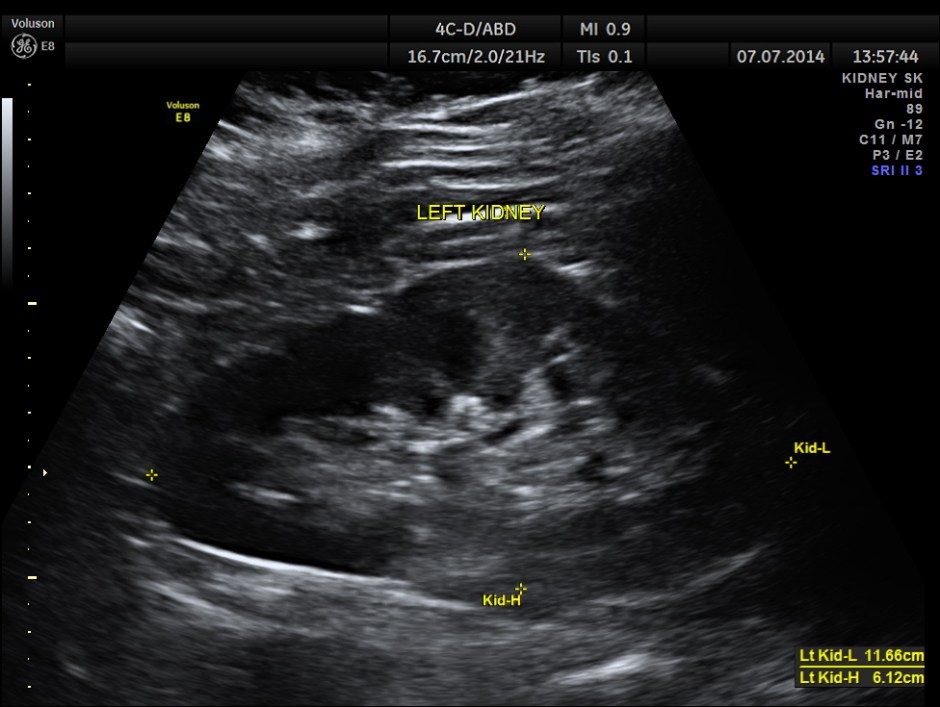

The left kidney appears to be normal.